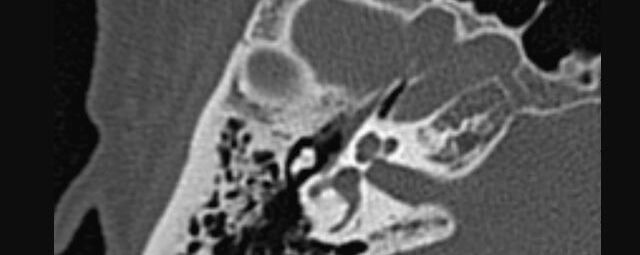

• Nasennebenhöhlen (Entzündungen, Tumore)

Thorax (Brustkorb)

• Entzündungen oder Tumore des Mediastinums und der Lunge

• Lungenembolie- Diagnostik

• hochauflösende Darstellung des Lungenparenchyms zur Abklärung chronischer interstitieller Erkrankungen wie z. B. Fibrosen, Emphysem, Bronchiektasen